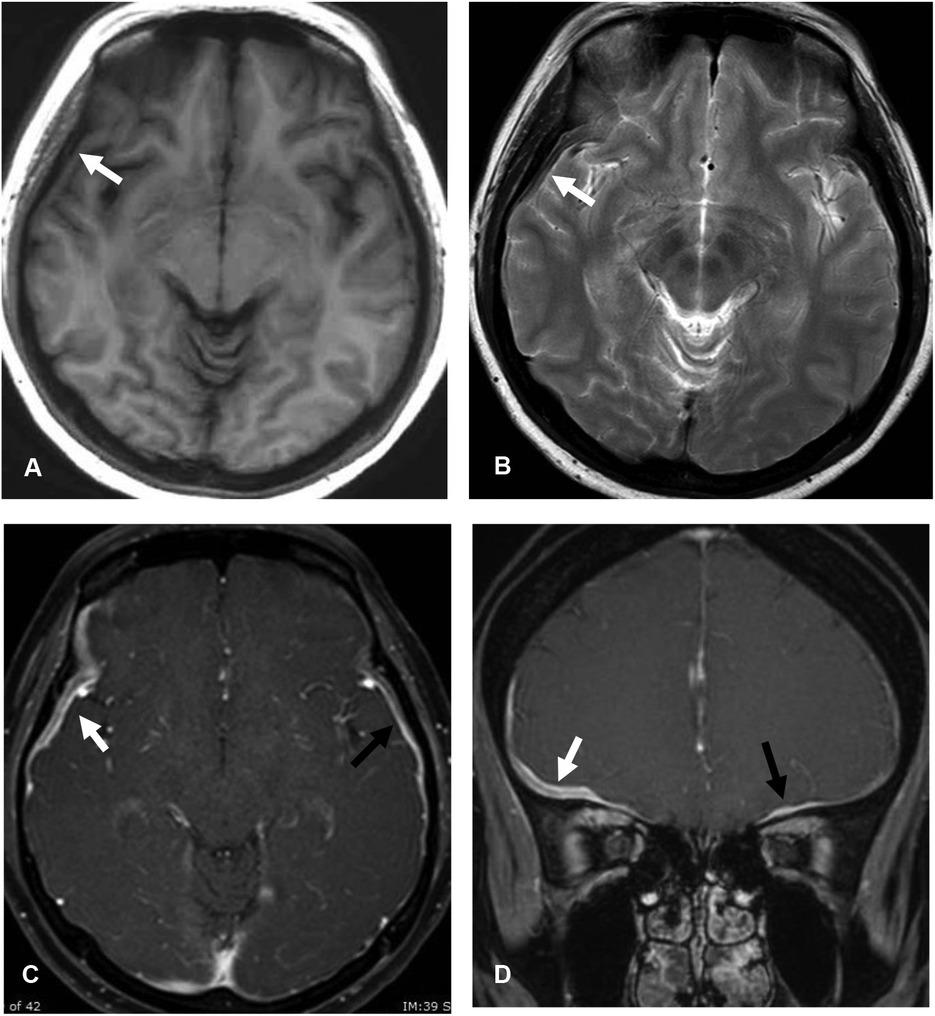

Configurations and locations of dural thickening in idiopathic HP and secondary HP groups

| Characteristics | Idiopathic HP | Secondary HP | P |

|---|---|---|---|

| (N = 23) | (N = 11) | ||

| n (%) | n (%) | ||

| Configurations | |||

| Linear/smooth | 12 (52) | 6 (55) | 1.00 |

| Nodular/undulated | 11 (48) | 5 (45) | 1.00 |

| Locations | |||

| Supratentorial lesions | 22 (96) | 11 (100) | 1.00 |

| Cavernous sinus | 13 (57) | 6 (55) | 1.00 |

| Orbital apex | 4 (17) | 4 (36) | 0.388 |

| Supraorbital foramen | 1 (4) | 0 | 1.00 |

| Sphenoid wing | 2 (9) | 2 (18) | 0.58 |

| Cerebral convexity | 8 (35) | 7 (64) | 0.151 |

| Tentorium cerebelli | 9 (39) | 5 (46) | 1.00 |

| Falx cerebri | 4 (17) | 2 (18) | 1.00 |

| Anterior and middle cranial fossae | 3 (13) | 6 (55) | 0.033* |

| Infratentorial lesions | 6 (26) | 0 | 0.145 |

| Posterior fossa | 6 (26) | 0 | 0.145 |

| Foramen magnum | 0 | 0 | |

| Diffuse | 6 (26) | 0 | 0.145 |

| Spinal canal | 1 (4) | 0 | 1.00 |